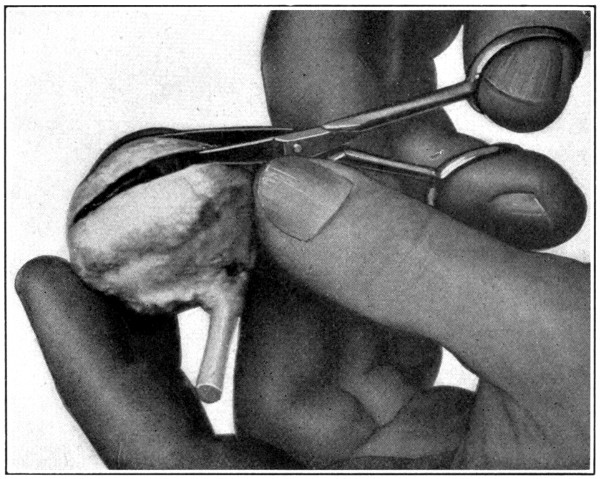

With a pair of dissecting forceps pinch up the sclerotic about 5 mm. anterior to the equator. With a pair of small, fine-pointed scissors, make an incision. (Fig. 2.) Next hold the eye in the left hand without exerting any pressure. Insert the point of the scissors into the incision which has been made, and cut. Be careful to keep the point of the scissors close to the sclerotic or an untimely puncturing of the choroid will occur. (Fig. 3.) Continue the[28-

cutting on a line parallel to the equatorial meridian and about 5 mm. anterior to it until about half the sclerotic has been separated. In cutting, always move the point of the scissors forward with a slight oscillating lateral movement. (Fig. 4.) While doing this, partly suspend the eyeball from the point of the scissors. Doing these things will tend to loosen[30] the choroid from the sclerotic and prevent puncturing too soon the former mentioned membrane. Now apply pressure in such a manner that the lips of the cut sclerotic will gap. Into this put the point of the scissors and very carefully pick up the choroid and the retina with the point of the scissors and cut[31] them. (Fig. 5.) If the choroid alone has been picked up and separated, the retina will show milky white or yellowish white underneath. The retina must then also be separated. Care must be taken not to go deeper than the retina or the hyaloid may be damaged. Continue the cutting of the choroid and the retina for a distance of about 20 mm. Apply enough pressure occasionally so that the vitreous will be[32] forced upward and above the cut choroid and the retina. This will show whether any strands of the two membranes have been left uncut. If the separation is complete for the distance specified above, invert the eyeball, squeeze and shake gently over some receptacle, such as a Stender dish, three-fourths filled[33] with a 2½ or 5 per cent. solution of formaldehyde, and the hyaloid membrane containing the vitreous, its attachments, suspensory ligament to the lens capsule, and lens, will drop out intact, as when one empties the contents of an egg. (Fig. 6.)

Fig. 5—Picking up the choroid with the point of the scissors.